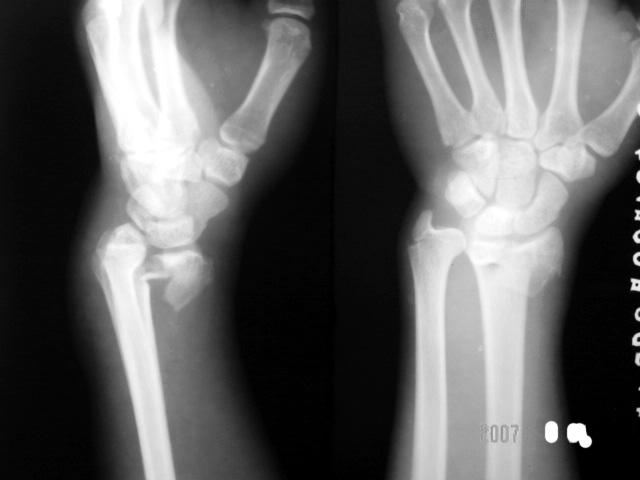

标题: X2074:[分享]smith骨折,男、17Y、外伤

男、17y、外伤

应该是smith骨折伴腕关节脱位

smith骨折,累及关节面。

应该是巴尔通骨折(桡骨远端骨折伴腕关节脱位)

典型巴通氏骨折